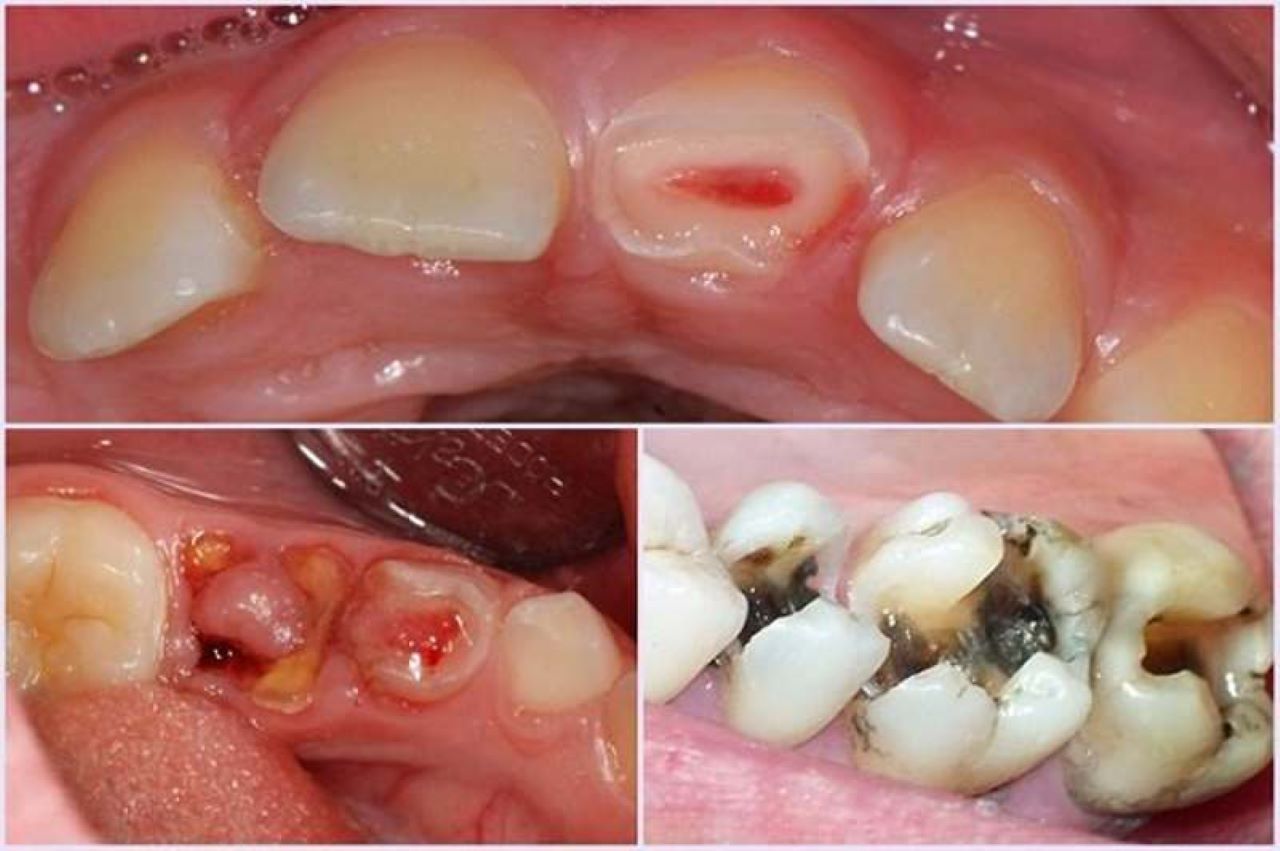

Răng sâu lồi thịt, hay còn gọi là áp xe răng – một biểu hiện của tình trạng viêm cấp tính nghiêm trọng. Phần nướu xuất hiện cục thịt dư do răng bị sâu lâu ngày không được điều trị. Cục thịt này chính là vùng niêm mạc sưng to, chảy mủ và được các chuyên gia coi là một dạng áp xe răng nghiêm trọng gây ảnh hưởng đến tủy, thậm chí có thể dẫn đến chết tủy.

Khi lượng mủ tăng lên, áp lực bên trong xương hàm lớn dần. Mủ sẽ phá hủy xương ổ răng, xuyên qua màng xương và nướu để tìm đường thoát. Kết quả là một khối sưng đỏ, mềm, đôi khi có đầu trắng – nhìn giống “cục thịt lồi”.

Đây không phải thịt thừa, mà là ổ nhiễm trùng đang hoạt động.

Nguyên nhân chính dẫn đến răng sâu lồi thịt là do không điều trị kịp thời khi răng bắt đầu bị sâu. Theo thời gian, ổ viêm nhiễm lan rộng, xâm nhập vào nướu khiến phần nướu bị vi khuẩn tấn công, dẫn đến hoại tử, tạo thành lỗ dò. Vùng niêm mạc xung quanh lỗ rò sẽ viêm mủ và sưng to, trồi ra ngoài giống như cục thịt.